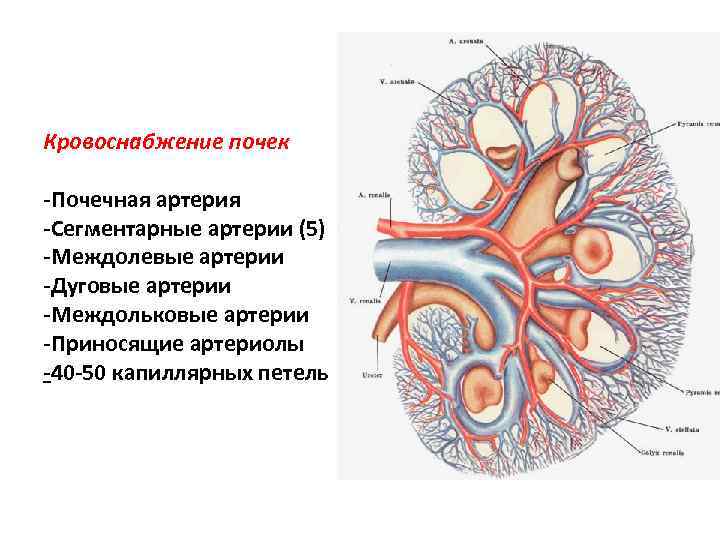

Кровоснабжение почек -Почечная артерия -Сегментарные артерии (5) -Междолевые артерии -Дуговые артерии -Междольковые артерии -Приносящие артериолы -40 -50 капиллярных петель

Кровоснабжение почек -Почечная артерия -Сегментарные артерии (5) -Междолевые артерии -Дуговые артерии -Междольковые артерии -Приносящие артериолы -40 -50 капиллярных петель

Особенности кровоснабжения почек 1. Наличие двух капиллярных сетей: капилляры сосудистых клубочков и капилляры, оплетающие канальцы нефрона. 2. В капиллярах сосудистых клубочков газообмен не происходит, в результате по выносящим артериолам оттекает артериальная кровь (чудесная артериальная сеть) 3. Так как диаметр выносящих артериол меньше, чем приносящих, в капиллярах сосудистых клубочков создается высокое гидростатическое давление (70 -90 мм. рт. ст. )

Особенности кровоснабжения почек 1. Наличие двух капиллярных сетей: капилляры сосудистых клубочков и капилляры, оплетающие канальцы нефрона. 2. В капиллярах сосудистых клубочков газообмен не происходит, в результате по выносящим артериолам оттекает артериальная кровь (чудесная артериальная сеть) 3. Так как диаметр выносящих артериол меньше, чем приносящих, в капиллярах сосудистых клубочков создается высокое гидростатическое давление (70 -90 мм. рт. ст. )